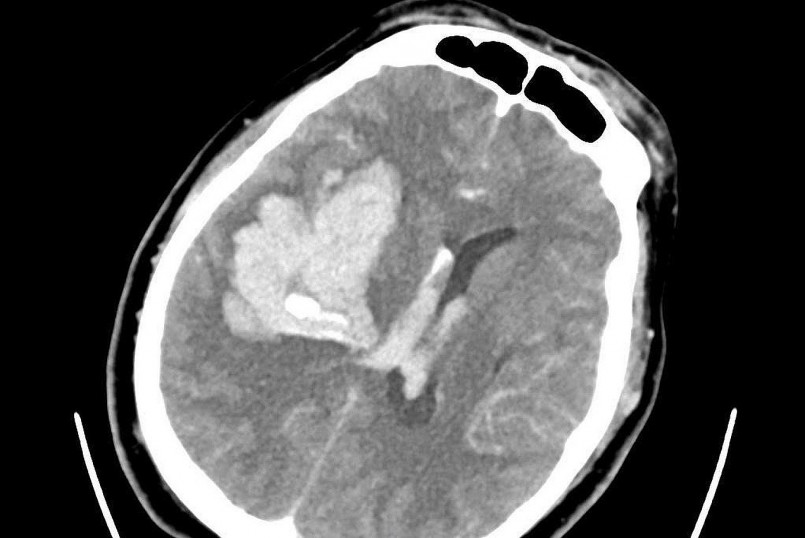

| Ảnh chụp CT cho thấy bệnh nhân bị xuất huyết não nặng (Ảnh: BS). |

Khi ê-kíp cấp cứu tiếp cận, bệnh nhân đã lơ mơ, liệt hoàn toàn nửa người trái, mất khả năng ngôn ngữ và huyết áp đo được cực kỳ cao: 248/184 mmHg. Kết quả CT não cho thấy bệnh nhân bị xuất huyết não diện rộng.